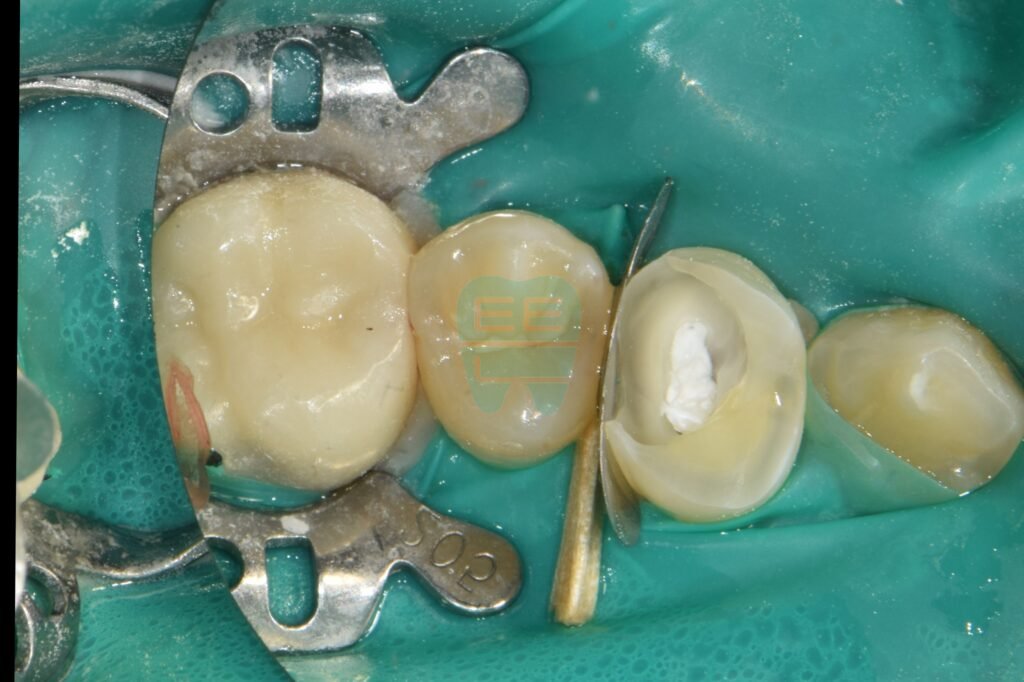

3. 러버댐 장착 & 레진 벽(Wall) 세우기 (핵심 과정

)

이 과정이 오늘 치료의 하이라이트입니다. 신경치료(근관치료)를 하려면 소독약이 새지 않고 침이 들어가지 않도록 ‘밀폐’가 되어야 하는데, 치아 벽이 다 무너져서 불가능한 상황이었죠.

그래서 러버댐을 걸고, 무너진 치아 주변에 단단한 레진으로 가짜 벽(Wall)을 만들어줍니다.

“왜 이렇게 복잡하게 하나요?” 이 ’레진 벽’이 있어야 러버댐을 걸 수 있고, 러버댐을 걸어야 세균 없이 깨끗하게 신경치료를 마무리할 수 있기 때문입니다. 이 과정이 귀찮아서 생략하면, 치료 도중 세균 감염으로 결국 치아를 뽑게 될 확률이 높습니다